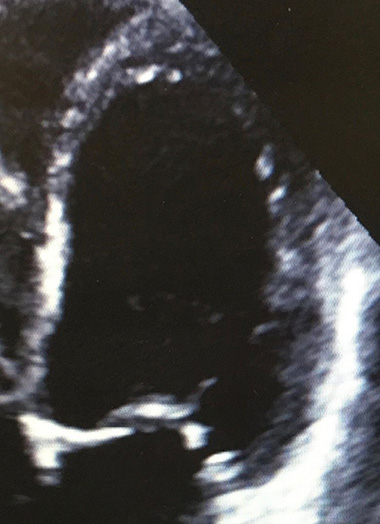

Transthoracic echocardiogram- left ventricle and mitral valve

There are many medical treatments available for this condition to both reduce symptoms and hospital admissions but also to improve survival. This usually starts with loop diuretics, ACE inhibitors, beta-blockers, mineralocorticoid antagonists (MRA) and Ivabradine. There are newer drugs available including Sacubitril-Valsartan which may be beneficial in selected patients. Some patients who haven't responded to medical treatment or whom are deemed to be at increased risk of life-threatening ventricular arrhythmia may require invasive procedures such as biventricular pacemaker/defibrillator insertion.